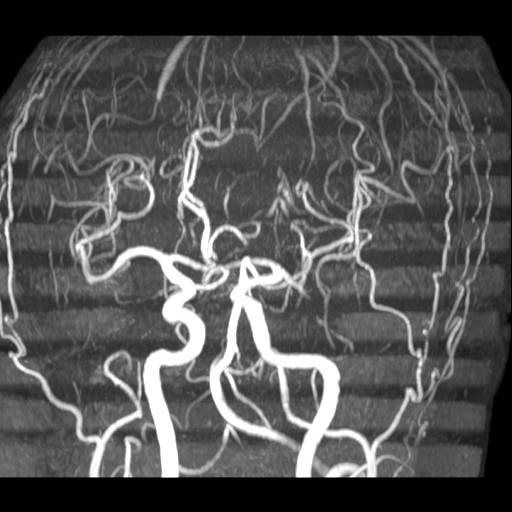

Hjerne, Normal, MR-angiografi

Normal karundersøgelse (angiografi) af hjernen.